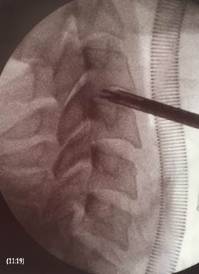

Fluoroscopic intraoperative lateral image of cervical spine. Note the endoscopic forceps decompressing the intervertebral disc.